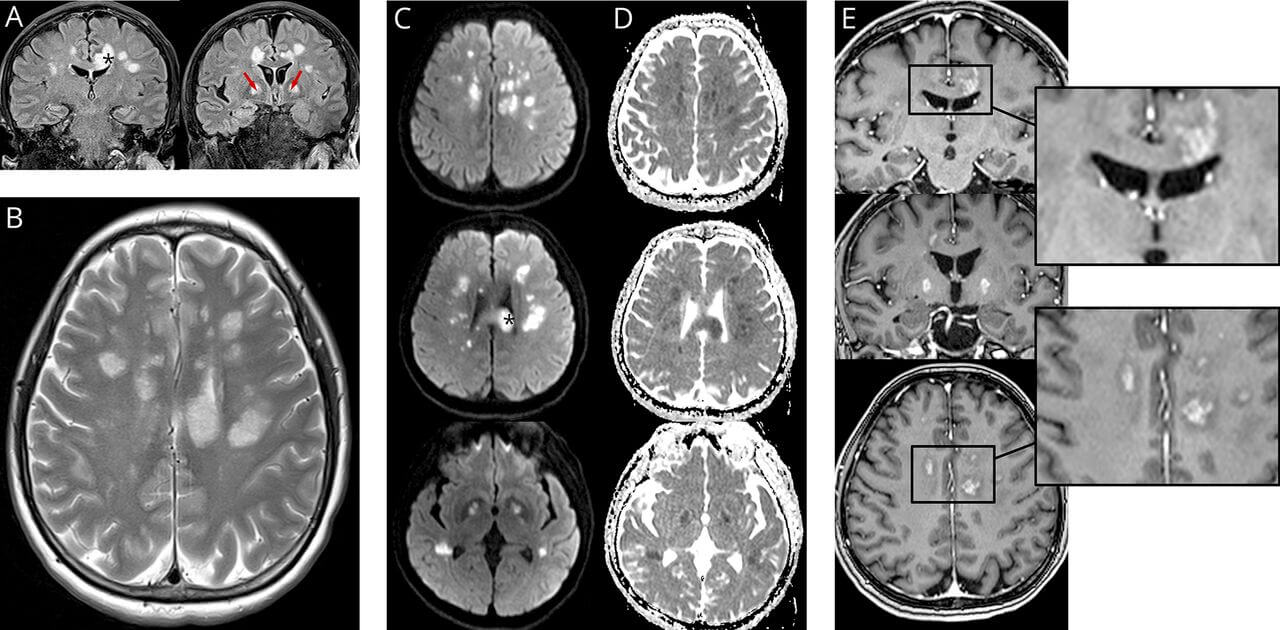

МРТ-скан мозга пациента с COVID-19. Данные исследования 2020 года, опубликованы в журнале Neurology

Авторы научной работы отмечают, что это первое исследование, в котором сравниваются снимки мозга как до, так и после того, как у испытуемого был диагностирован COVID-19. Потерю серого вещества исследователи обнаружили сразу в трех областях мозга.

«Полученные результаты последовательно связаны с потерей серого вещества в областях лимбической коры – областях мозга, связанных с восприятием вкусов и запахов».

В долгосрочном эксперименте, в котором приняли участие 782 добровольца, сравнивалось сканирование мозга людей до пандемии. Для аналогии между предпандемическим и постпандемическим сканированием мозга исследователи затем пригласили 394 перенесших COVID-19 вернуться для последующего сканирования, а также 388 здоровых добровольцев.

Среди тех участников, которые выздоровели от COVID-19, исследователи увидели значительное влияние вируса на серое вещество, точнее на его потерю в трех областях мозга с течением времени. Серое вещество позволяет людям контролировать движение, память и эмоции, поэтому выявленная аномалия может оказать влияние на коммуникативные навыки и клетки мозга.

Следует также отметить, что исследование еще не подверглось тщательной экспертной оценке и опубликовано на сервере препринтов. Работа, однако, предполагает, что потеря серого вещества в областях мозга, связанных с памятью, «может увеличить риск развития деменции у этих пациентов в долгосрочной перспективе».

Этот вывод следует за исследованием, опубликованным журналом Lancet Psychiatry journal в прошлом году, предполагающим, что серьезные инфекции COVID-19 могут повредить мозг, что приведет к долгосрочным осложнениям, таким как инсульт или симптомы, подобные деменции. Однако авторы отметили, что для адекватной оценки влияния COVID-19 на здоровье мозга необходимо больше данных.

Отмечу также, что большинство из тех, кто принимал участие в исследовании сообщили о легких или умеренных симптомах или не имели их вообще. Как сообщает Reuters, ученые также не могут подтвердить, является ли потеря серого вещества результатом распространения вируса в мозг или каким-либо другим эффектом болезни.